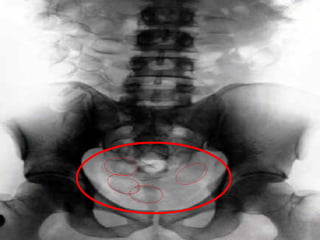

Cápsulas   de   Cocaína   engolidas   Veja o Raio X...